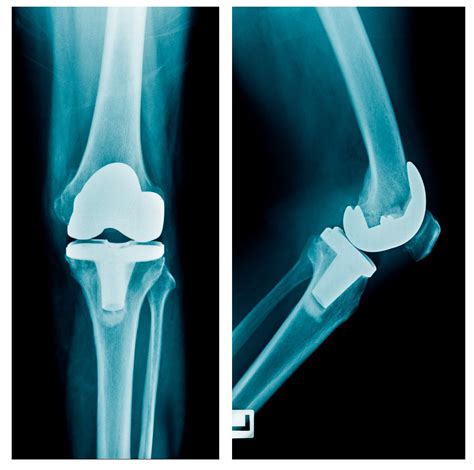

Knee replacement images play a crucial role in the diagnosis, planning, and execution of knee replacement surgery. These images provide valuable insights into the condition of the knee joint, helping surgeons to make informed decisions. Here are some key points about the importance of knee replacement images:

• Diagnostic Tool: Knee replacement images, such as X-rays, MRIs, and CT scans, help diagnose the extent of damage to the knee joint. These images can reveal bone spurs, cartilage loss, and other abnormalities that indicate the need for surgery.

• Preoperative Planning: Surgeons use knee replacement images to plan the surgical procedure. By studying the images, they can determine the size and type of implants needed, as well as the best approach for the surgery.

CT Scan Create 3D models of the knee joint Enhances surgical precision

Here is an example of knee replacement images that highlight the benefits of the procedure:

Knee Replacement Benefits

📸 Note: The images above are for illustrative purposes only. Always consult with a healthcare provider for personalized information.